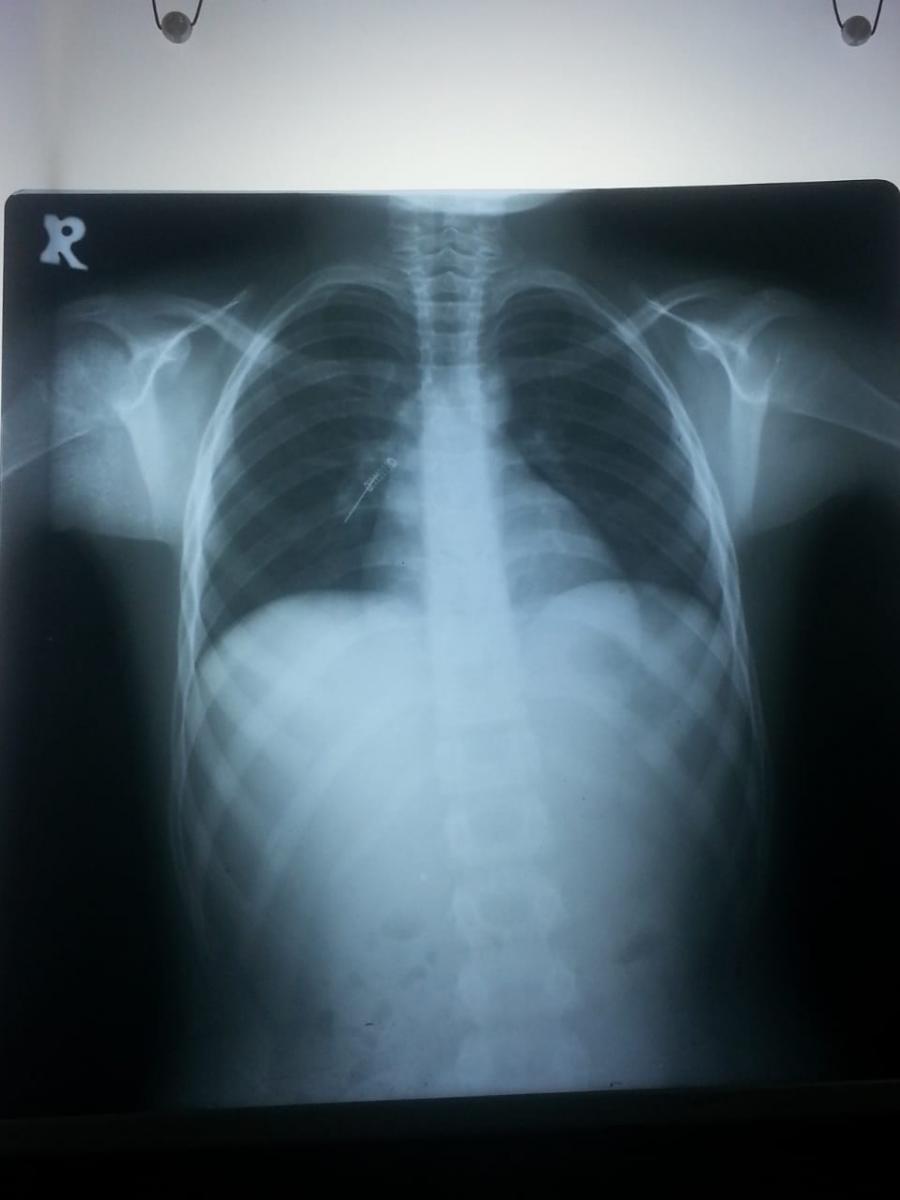

The authors present the case of the extraction of a double metal foreign body following inhalation by a 4-year-old child (metal pin and metal spiral shaped object) in his right bronchus.

A foreign body (FB) inhalation is a common event, especially among children and young adults. Two metallic FB inhalations in children have rarely been described. The authors report the child's case who presented to the accident and emergency department with a two-hour history of choking and coughing while playing with his sister. There were no signs of respiratory distress. A plain chest x-ray demonstrated double radio-opaque shadows inside the RT bronchus intermediate. A rigid bronchoscopy was performed under general anesthesia, and the two metallic objects were removed. The procedure was uneventful and the child was discharged six hours after in good general condition.